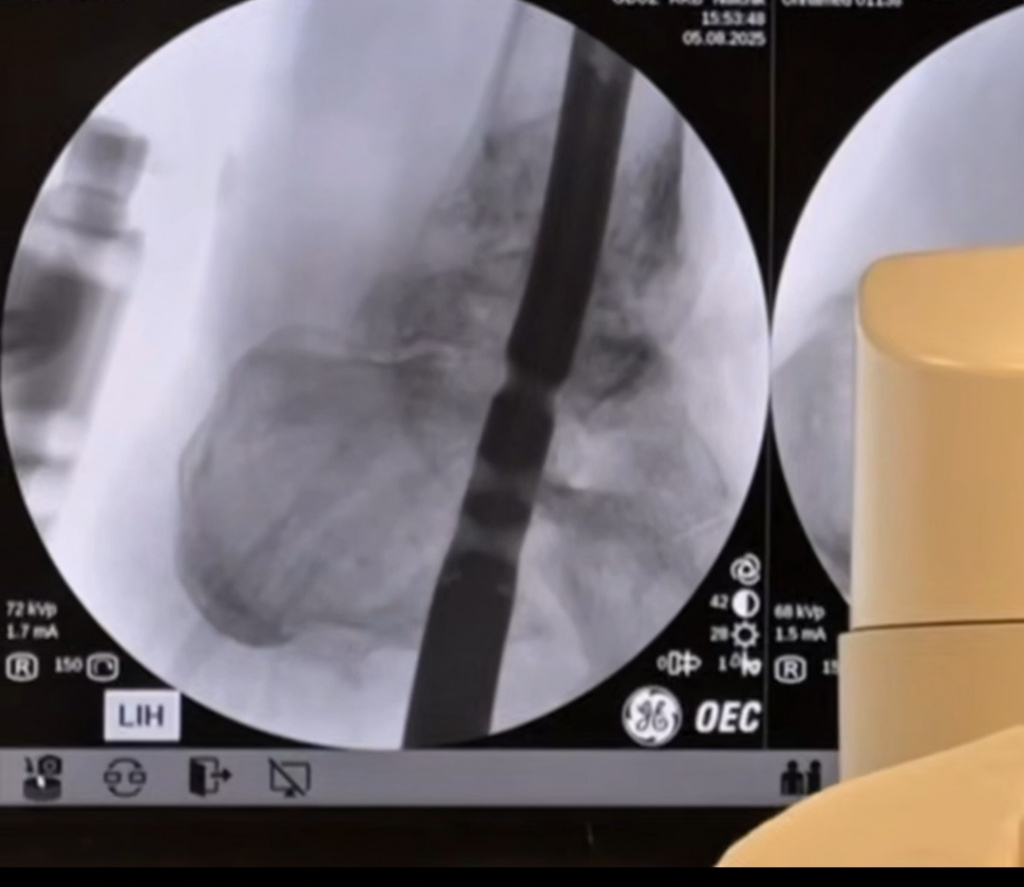

Благодаря наличию современного оборудования и высокой квалификации хирургической бригады РКБ, стало возможным проведение комплексной и эффективной операции. В ходе вмешательства хирурги устранили деформацию сустава и зафиксировали его в оптимальном положении для обеспечения неподвижности и последующего восстановления. Для стабилизации и фиксации была использована технология интрамедуллярного стержня, который вводится в костномозговую полость. Образовавшийся костный дефект был устранен с помощью аутотрансплантата – биологического материала, взятого у самого пациента для пересадки, что минимизирует риск отторжения и способствует более быстрому восстановлению.